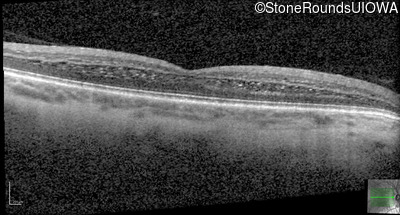

Age at visit: 26 years

This 26 year old man had significant myopia since childhood and uncorrectable reduction of acuity since his mid teens. Optic nerve abnormalities were noticed on a routine exam at age 5 and a diagnosis of Retinitis Pigmentosa was suggested. His medical history is also positive for profound hearing loss at birth and type 1 diabetes mellitus.